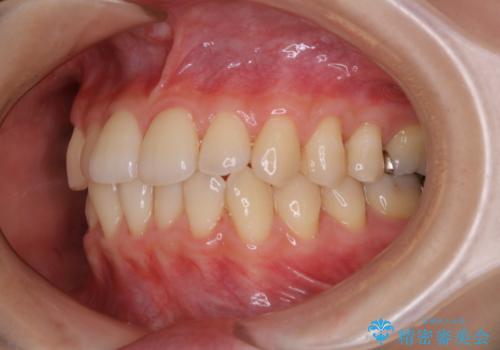

矯正治療が終わったタイミングでPMTC